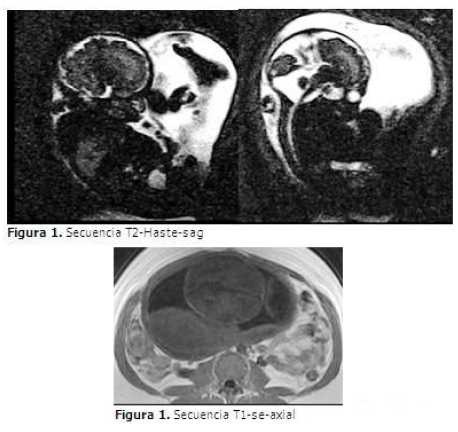

Se apreció, en secuencias T1-se-sag-axial, T2-Haste-sag, una masa pequeña con irregularidad, abombada, con salida de canal posterior cervico dorsal. Iso-hipo intensos en T1 y hiperintenso en T2 stir con toma del canal intervertebral, que además desplazaba hacia atrás y comprimía el cordón medular, asociado a cambios en la intensidad de señal de los músculos adyacentes. Corte sagital: pérdida del paralelismo de la columna. Corte axial: el canal espinal se observa en forma de U. Abierto. (Figura 1).

Secuencia T2-Haste-sag

Secuencia T1-se-axial

Se concluyó el diagnóstico como malformación del tubo neural (mielomeningocele).